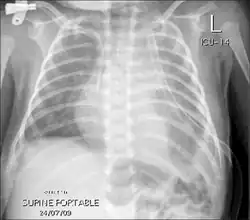

Chest X-rays can detect a chylothorax. It appears as a dense, homogeneous area that obscures the costophrenic and cardiophrenic angles. Ultrasounds can also detect a chylothorax, which appears as an echoic region that is isodense with no septation or loculation. However, neither a normal chest x-ray nor an ultrasound can differentiate a chylothorax from any other type of pleural effusion.[5]

Chest X-ray showing bilateral chylothorax